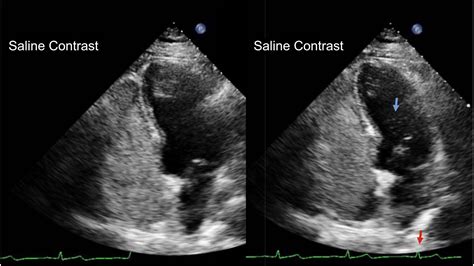

When you experience unexplained symptoms such as migraines, dizziness, or a history of stroke without a clear cause, your cardiologist might recommend specialized diagnostic imaging. Among the most effective tools for uncovering hidden cardiac abnormalities is the Echo With Bubble Study. This specialized diagnostic procedure, often referred to as a bubble echocardiogram, is designed to detect small openings or shunts within the heart that standard imaging might miss. By enhancing the ultrasound images with a simple saline-based contrast agent, physicians can visualize the flow of blood through the heart chambers in real-time, providing critical data to guide your treatment plan.

To perform the bubble study, a technician or nurse prepares a mixture of sterile saline (saltwater) agitated with a tiny amount of the patient’s own blood or air. This creates microscopic bubbles. When this solution is injected into a vein in your arm, it travels to the right side of the heart. If the heart is functioning normally, these bubbles are filtered out by the lungs. If there is a hole in the heart, some of these bubbles will cross over into the left side of the heart, becoming visible on the ultrasound monitor.

The results of your Echo With Bubble Study are categorized based on how many bubbles appear in the left atrium after the injection. A "negative" study means that the bubbles remained contained within the right side of the heart, suggesting there is no significant communication between the atria. A "positive" study indicates that bubbles were detected in the left atrium, confirming the presence of an intracardiac shunt.

If the result is positive, your cardiologist will grade the shunt based on the number of bubbles seen. This helps them determine the clinical significance of the finding. Not every PFO or ASD requires surgical intervention; many are asymptomatic and require no treatment at all. However, if the findings are linked to specific health events, your doctor might discuss medication, such as blood thinners, or a minimally invasive procedure to close the opening.